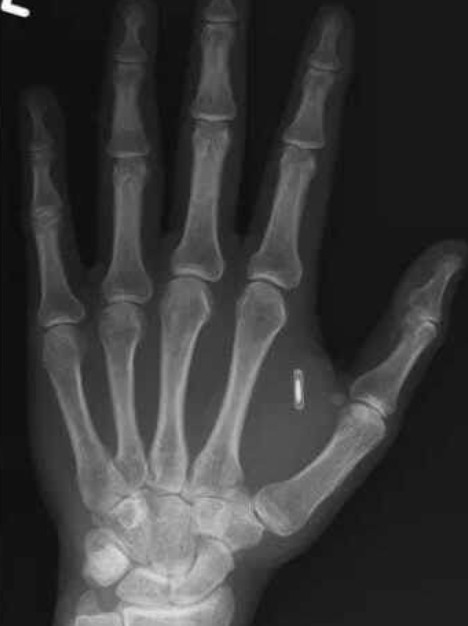

ABD’nin Missouri eyaletinde yaşayan bir illüzyonist ve moleküler biyolog olan Tzu Ten Wang, sıra dışı bir deney yapmaya karar verdi: Performanslarında kullanmak için elinin içine bir RFID çip implante etti. İlk başta her şey planlandığı gibi işliyordu. Seyirciler, Wang’ın eline akıllı telefonlarını dokundurduğunda ekranda önceden hazırlanmış “sihirli” bir efekt beliriyordu.

Daha da büyük bir sorun ise deneyin ilerleyen aşamasında ortaya çıktı: Wang, çipin parolasını unuttu. Böylece cihazın içindeki verilere erişim tamamen imkânsız hâle geldi. Çip çıkarılabiliyor olsa da işlem hem zahmetli hem de ek bir operasyon gerektirdiği için Wang için ciddi bir sorun oluşturdu.